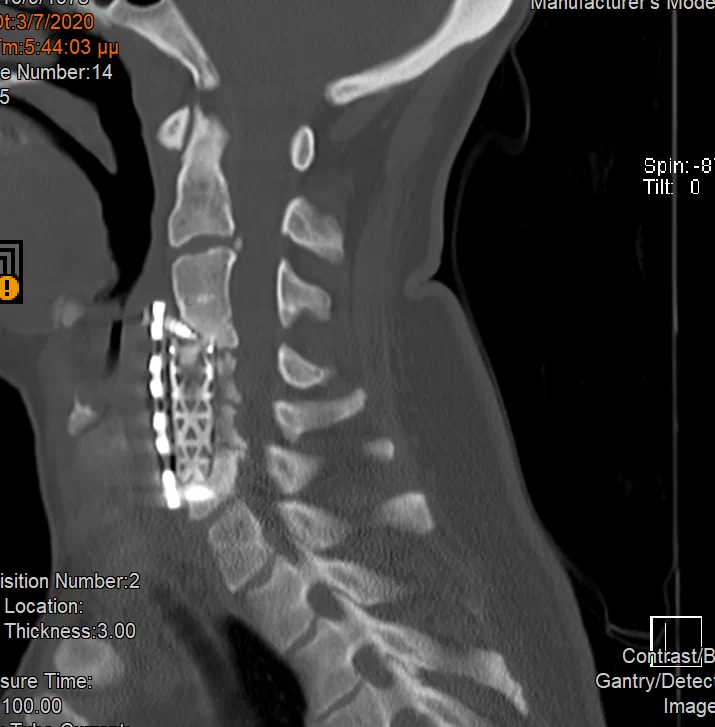

Ο απεικονιστικός έλεγχος με μαγνητική και αξονική τομογραφία της σπονδυλικής στήλης ανέδειξε εικόνα σωματεκτομής Α5, Α6 και μερικώς και Α7. Υπήρχε χαλάρωση των βιδών που καθήλωναν την πλάκα. Συνολικά εικόνα ψευδάρθρωσης και πίεσης επί του νωτιαίου μυελού και των αυχενικών ριζών (κυρίως Α7 δεξιά)

Διενεργήθηκε αρχικά οπίσθια σπονδυλοδεσία με διαυχενικές βίδες Α4, βίδες στα πλάγια ογκώματα Α5 και διαυχενικές βίδες Α7 και Θ1 ενώ έγινε και τρηματεκτομή Α6/7 δεξιά.

Στη συνέχεια, αφαίρεση της πρόσθιας πλάκας, ολοκλήρωση της σωματεκτομής Α5 & Α6, απελευθέρωση του νωτιαίου μυελου, πρόσθια δισκεκτομή Α7/Θ1 και τοποθέτηση πρόσθιας πλάκας Α4-Θ1.

Αρχικά έγινε οπίσθια σπονδυλοδεσία προκειμένω να στηριχθεί ο αυχένας της ασθενούς και να μειωθούν τα άλγη τα οποία οφείλονταν στην “αστάθεια” της αυχενικής μοίρας. Παράλληλα, διενεργήσαμε και οπίσθια τρηματεκτομή ώστε να εξασφαλίσουμε την απελευθέρωση της δεξιάς Α7 ρίζας, η οποία δημιουργούσε πόνο στην ασθενή. Όπως φαίνεται στη μετεγχειρητική αξονική τομογραφία, οι βίδες στους αυχένες του Α4 σπονδύλου τοποθετήθηκαν με ακρίβεια χιλιοστού. Σ’ αυτό, σημαντική ήταν η βοήθεια του διεγχειρητικού νευροπλοηγού σπονδυλικής στήλης με το πιο σύγχρονο σύστημα απεικόνισης (Ο-arm II)

Στη συνέχεια γυρίσαμε την ασθενή σε ύπτια θέση και αφού αφαιρέσαμε την παλαιά πλάκα, αποκαθηλώνοντας τον οισοφάγο, ολοκληρώσαμε τη σωματεκτομή και απελευθερώσαμε τα νευρικά στοιχεία και από μπροστά. Μια και δεν ήταν δυνατή η στήριξη της πλάκας στον Α7, αλλά ούτε και θέλαμε να καταλήξουμε ένα τεράστιο χάσμα, αποφασίσαμε να διατηρήσουμε τον Α7 και να διενεργήσουμε πρόσθια δισκεκτομή Α7/Θ1, καθηλώνοντας τελικά την πλάκα στον Α4, Α7 και Θ1 σπόνδυλο.